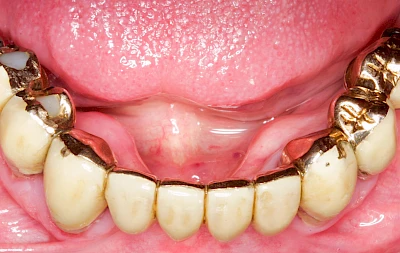

Überbeine im Bereich der Kiefer sind gar nicht so selten. Häufiger im Bereich der Seitenzähne unterhalb des Zahnfleisches, aber auch in der Mitte vom Gaumen. Überbeine haben in dem Sinne keinen Krankheitswert, müssen also nicht operativ entfernt werden, wenn diese nicht stören. Überbeine können ein Anzeichen für Knirschen und Pressen sein.